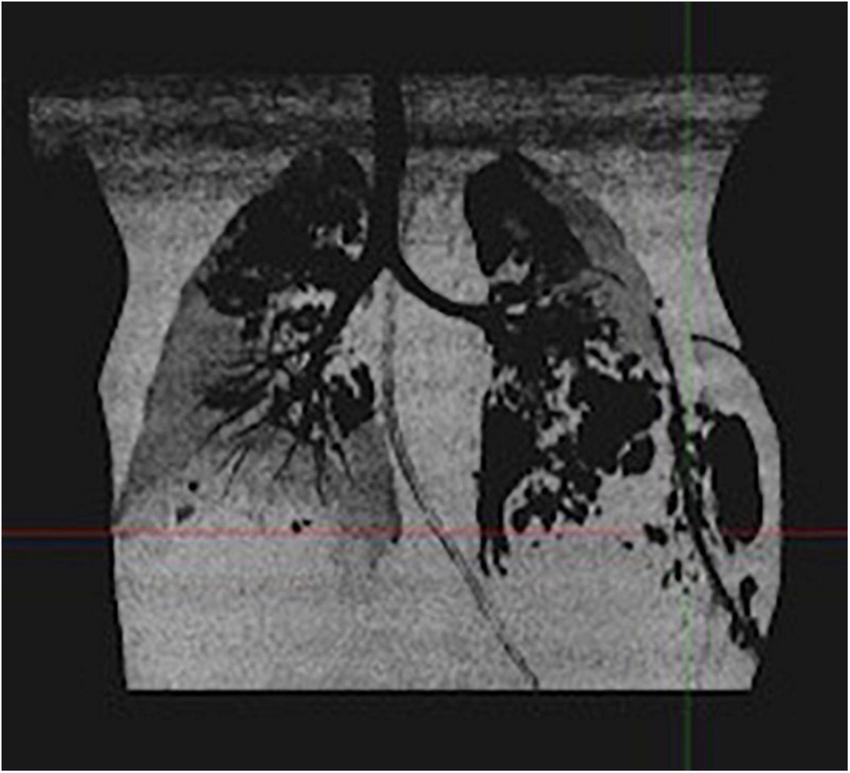

Gradually, pulmonary lesions turned into bilateral pneumatoceles and necrotizing pneumonia (Figure 1). The pleural drain was left in place for several days because of persistent pneumothorax secondary to bronchopleural fistulas.

FIGURE 1

Thoracic CT scan of case 1: bilateral pneumatoceles and necrotizing pneumonia.